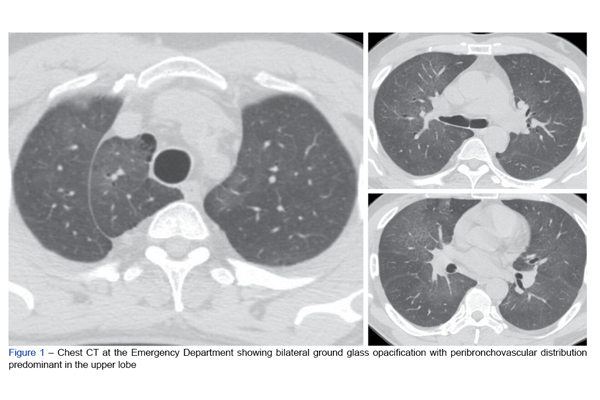

Introduction: The SARS-CoV-2 pandemic has reshaped the global landscape as we know it and had a tremendous effect on healthcare systems around the wor...